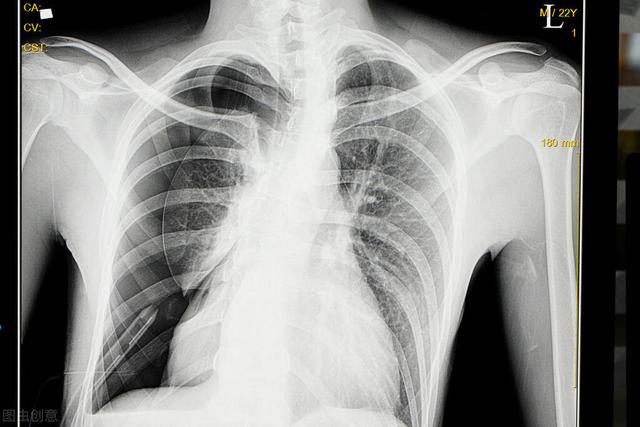

Il s'accompagne généralement de douleurs thoraciques et la gravité des symptômes varie en fonction de la quantité de gaz ; un grand nombre de pneumothorax peut entraîner des difficultés respiratoires évidentes, voire une insuffisance respiratoire, et le diagnostic est généralement confirmé par une radiographie du thorax, qui permet de voir le gaz dans la cavité pleurale.

En cas de suspicion de pneumothorax, le premier examen est l'imagerie, principalementRadiographie thoracique et tomodensitométrie thoracique. Une radiographie du thorax suffit généralement à confirmer la présence d'un pneumothorax et, pour certains patients, un scanner du thorax peut être réalisé.